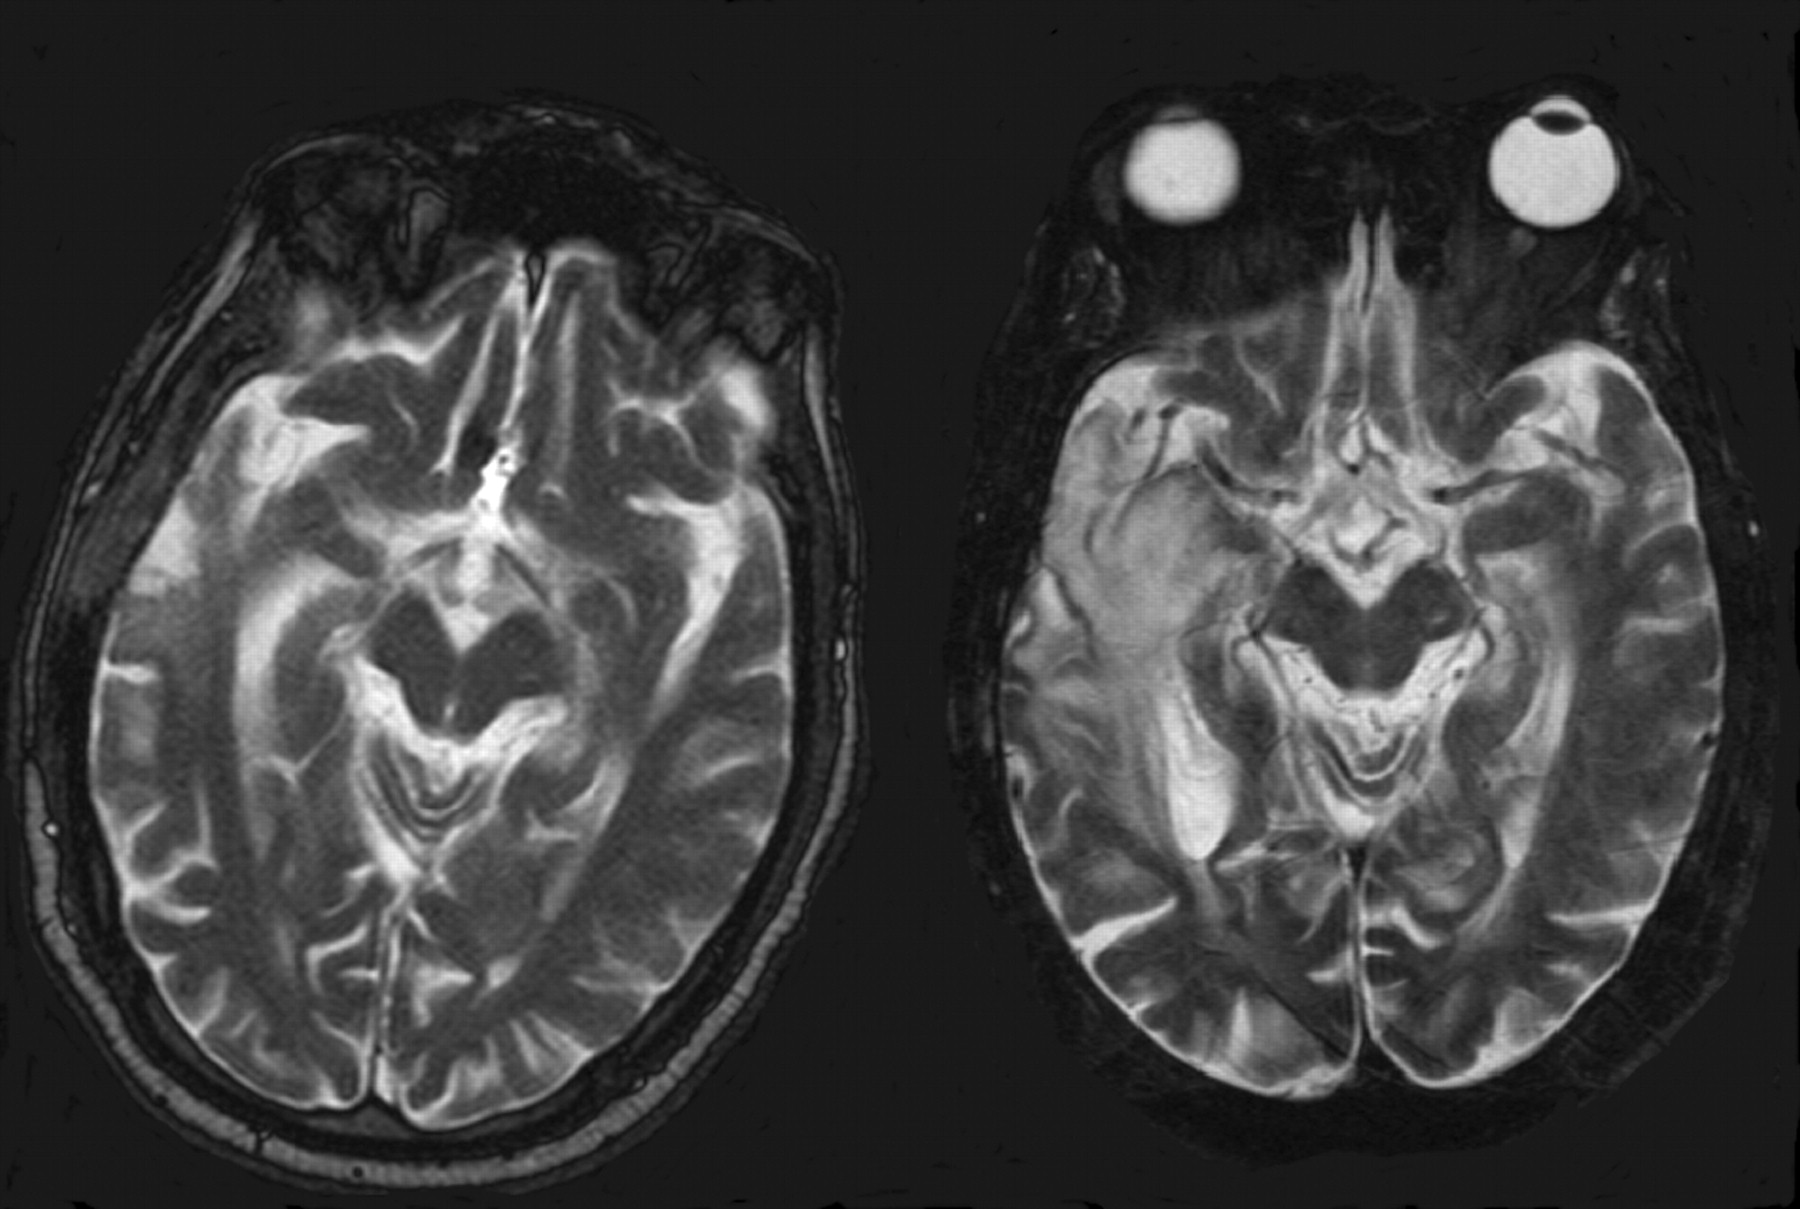

In all patients, the GSRTS device was clearly identified. The balloon was hyperattenuated on CT scans (Fig 2), reflecting the iodinated contrast material. It had low signal intensity on T1-weighted and FLAIR MR images and high signal intensity on T2-weighted MR images (Fig 3). On one CT study, the brain immediately around the balloon could not be seen because of artifacts (Fig 2). On all MR imaging studies, the brain adjacent to the balloons was well depicted with all sequences (Fig 3).

MR images obtained <48 hours after surgery.

A, Axial nonenhanced T1-weighted image (500/12/1) shows the hypointense balloon and central shaft (tube), with good visualization of surrounding tissues.

B, Axial contrast-enhanced T1-weighted image (500/12/1) shows the well-defined borders of the device and surroundingtissue, associated with thin enhancement of the surgical bed.

C, Corresponding axial T2-weighted image (5050/99/1) shows the hyperintense balloon. There is a small amount of ill-defined hyperintensity in adjacent tissues.

D, Corresponding axial FLAIR image (8000/110/1) shows the hyperintensity in the tissues around the balloon better. These areas are most likely residual vasogenic tumor edema and postsurgical changes.